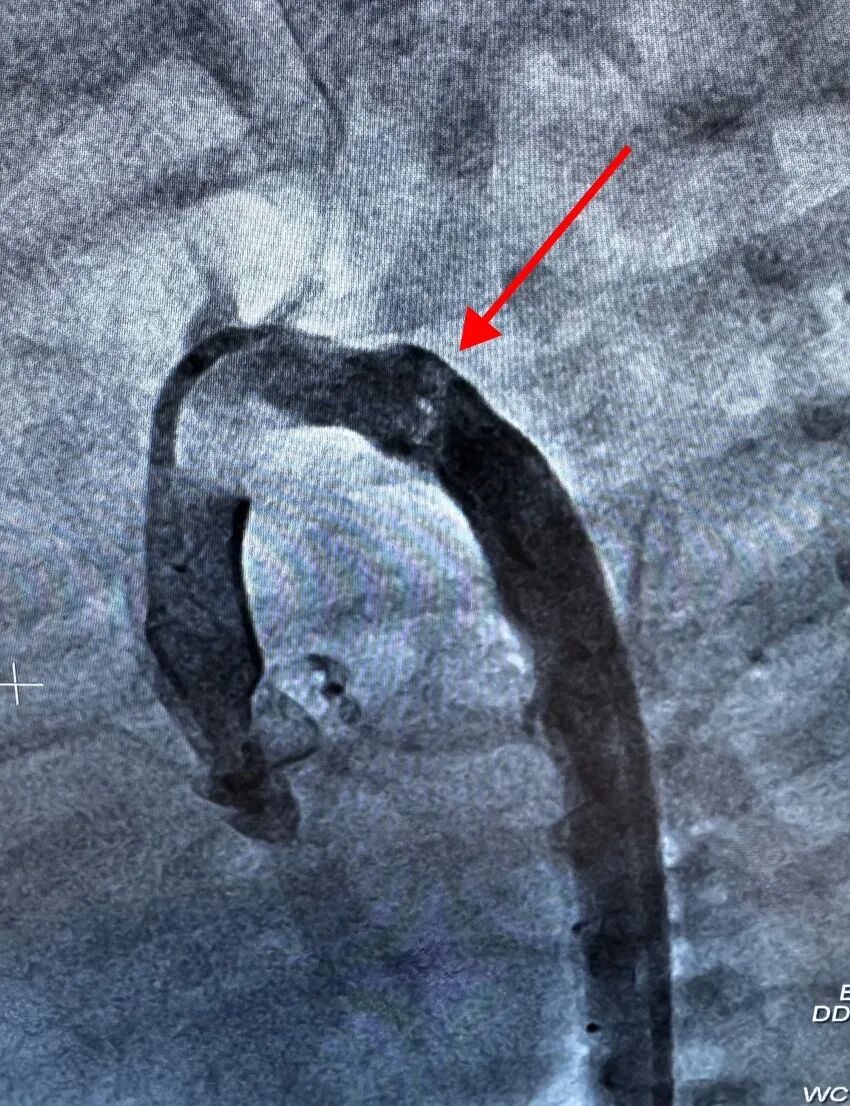

心导管室内,介入团队全神贯注,屏息操作,精准地将球囊送至预定位置。

每一个步骤都如履薄冰,每一个决策都关乎存亡,整场手术仿佛一场在方寸之间的精细雕琢。

扩张、观察、再评估......

“成了!”导管室外,团队成员看着影像说道。

主动脉最狭窄处由1mm扩张到近6mm,压差几乎为零,血流恢复了畅通,那条被堵塞的“生命主干道”终于被成功打通。手术成功!